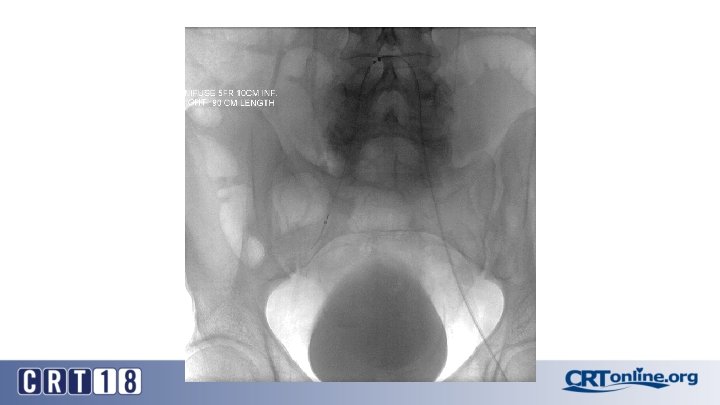

CS Compared to BMS in iliac occlusion • 2009 and December 2015, 128 iliac artery occlusions were stented • A CS was implanted in 78 iliac arteries (61%) and a BMS in 50 (49%) • After propensity score matching (lesion site and length separated and associated femoropopliteal disease included) (47 for each group). • Technical success was 98% • Complication rates same: 12% vs. 12%, p = 1. 0 • 30 day mortality rates same: 2% vs. 2%, p = 1. 0 Piazza M, et al. Outcomes of polytetrafluoroethylene-covered stent versus bare-metal stent in the primary treatment of severe iliac artery obstructive lesions. J Vasc Surg. 2015; 62(5): 1210 -8.

CS superior to BMS, in the right setting • At 36 months (average 23 ± 17) overall primary patency only approached significance: 87% vs. 66%, p =. 06 • For TASC D, CS: 88% vs. BMS: 54% (p =. 03) • Patency was in favor of CSs for occlusions > 3. 5 cm in length (p =. 04), total lesion length > 6 cm (p =. 04), and occlusion with calcification > 75% of the arterial wall circumference (p =. 01) • Kissing stent patency also superior with CS